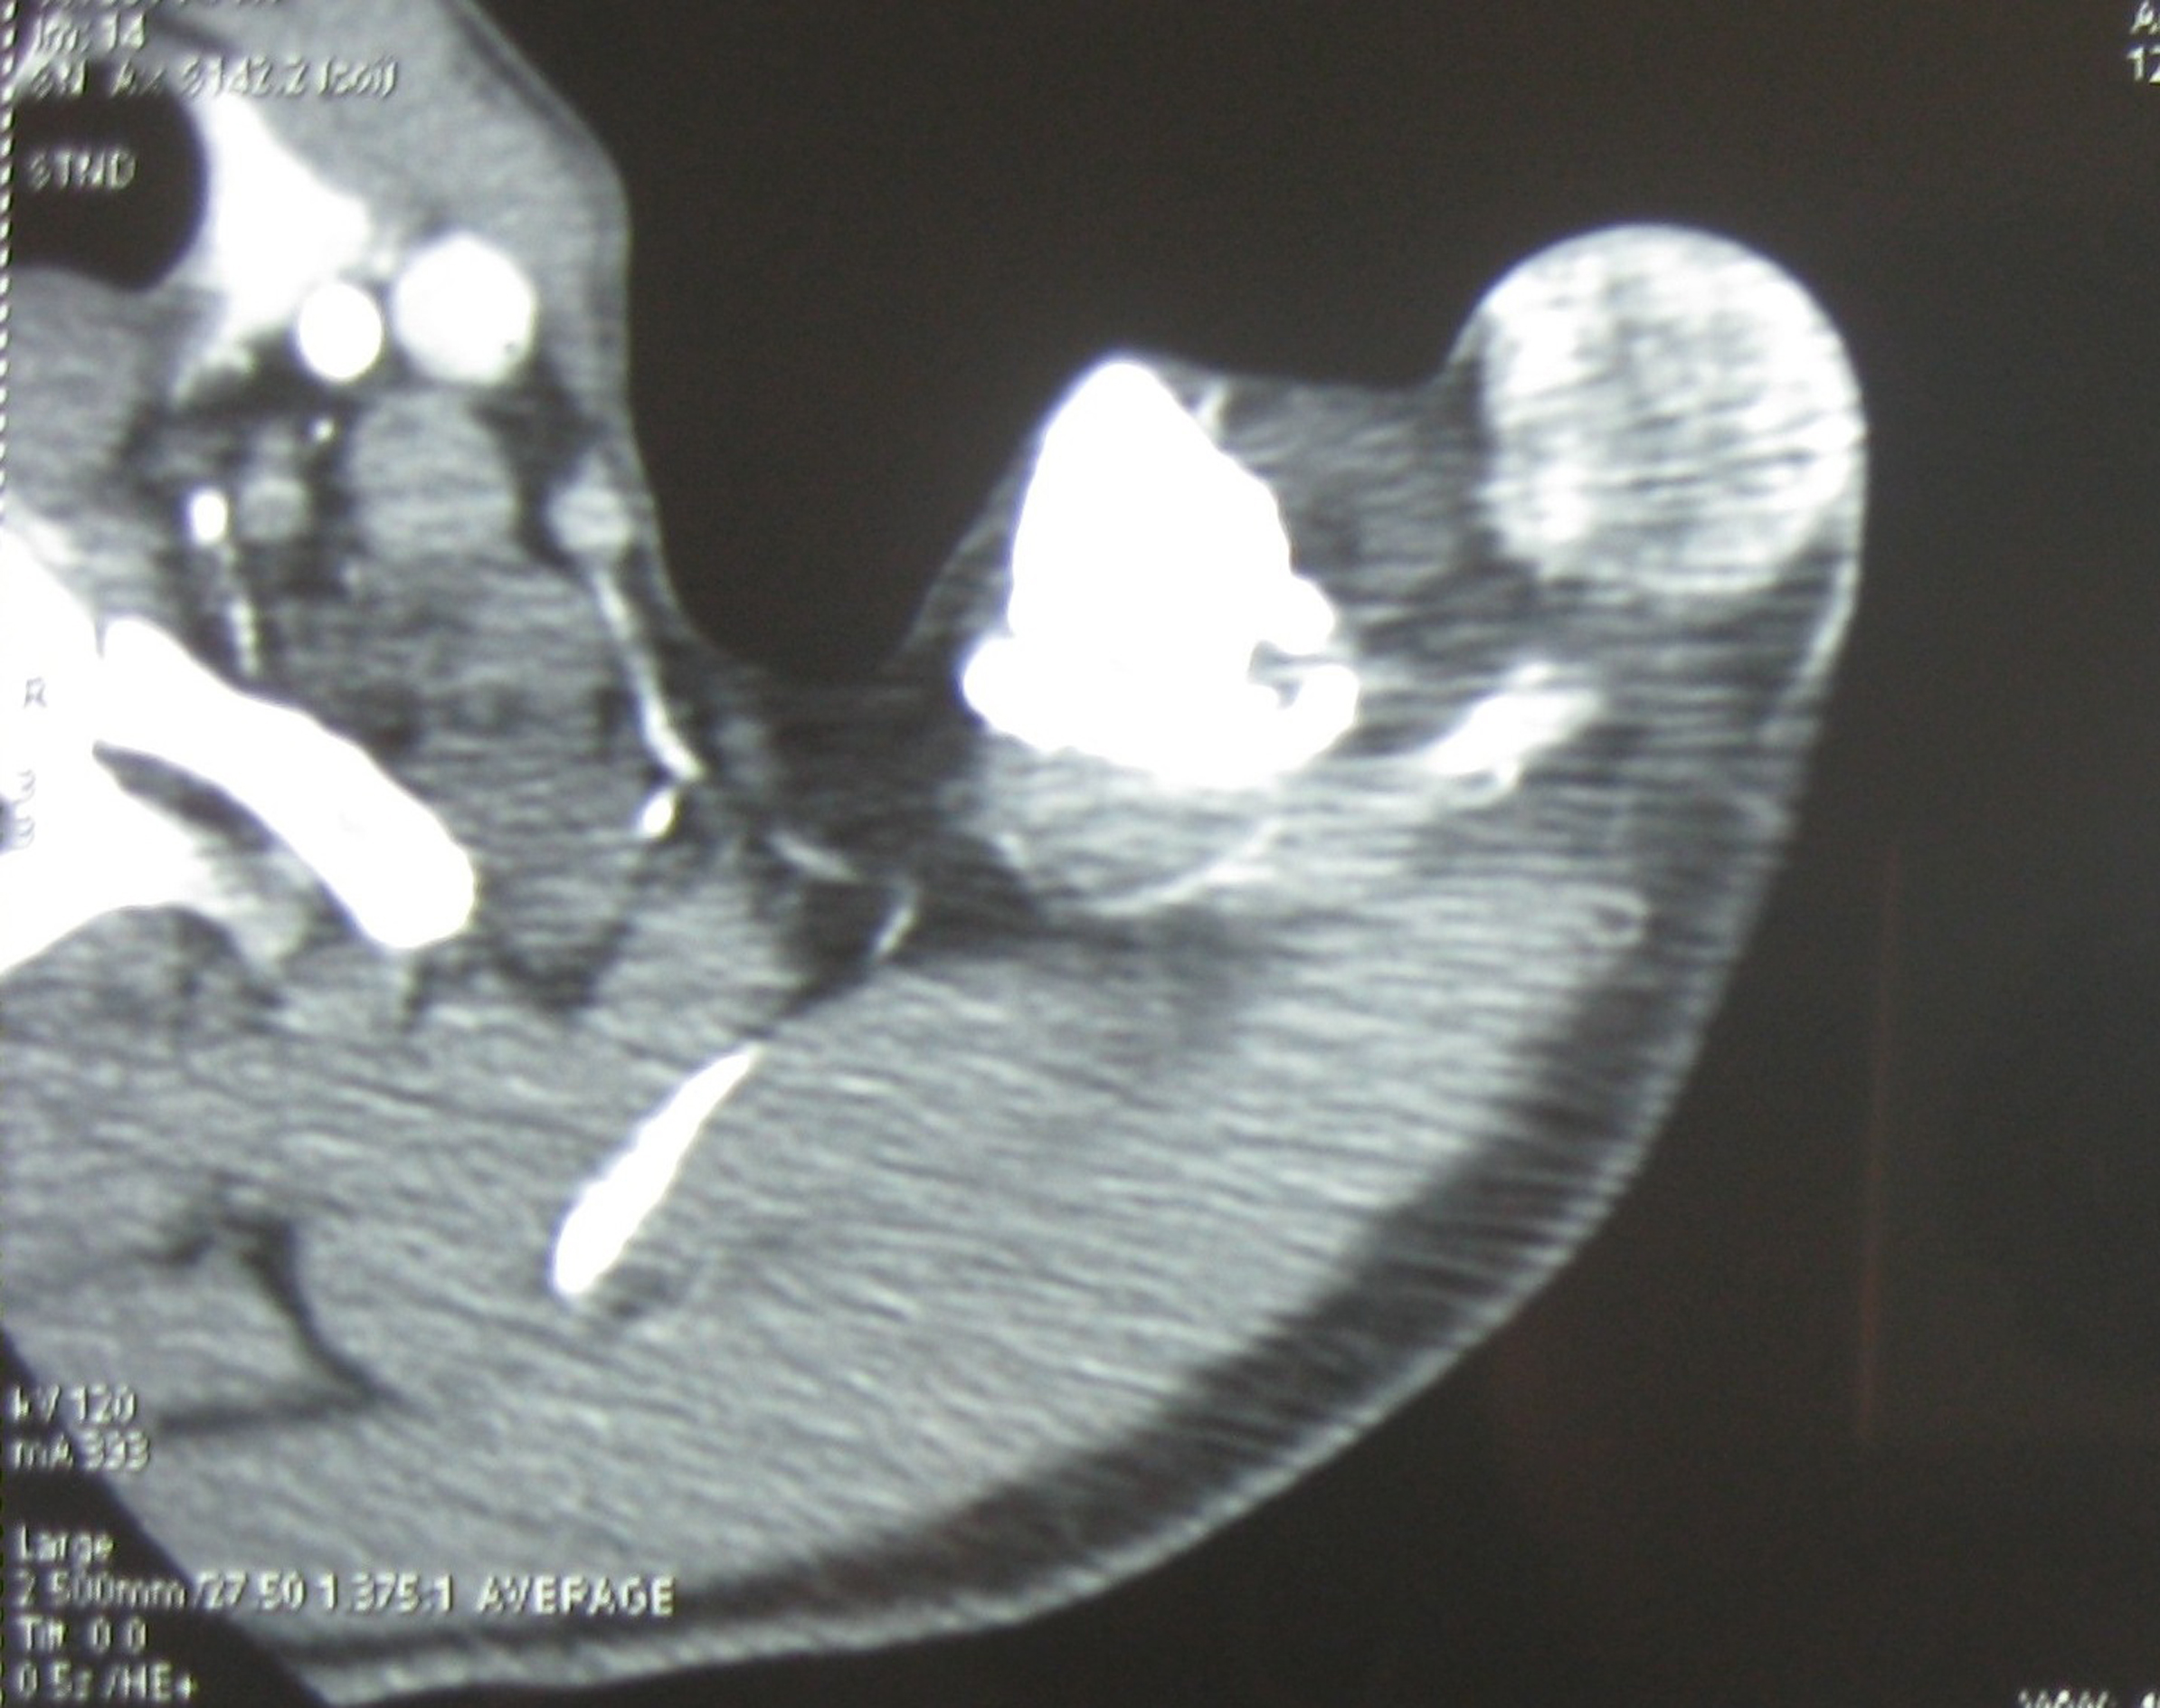

A 49-year-old man presented with a six-month history of a dermal and subcutaneous tumor of the left shoulder, without osseous involvement. Physical examination suggested a vascular tumor. An angioscan found a subcutaneous hypervascular and well circumscribed mass of the shoulder, without osseous involvement (Fig. 1). The rest of the physical examination and imaging exploration were normal. A surgical excision of the mass was performed. Macroscopically, it was a well circumscribed hemorrhagic lesion, which measured 6 x 3 x 1.5 cm. Histopathological examination showed a small round cell malignant tumor with extensive geographic necrosis, located in the dermis (Fig. 2a). Cellular atypia was seen (Fig. 2b) and occasional mitoses were seen with a count of four mitoses per 10 high power fields. Thin walled capillary often accompanied tumor cells. Immunohistochemical studies showed that the tumor cells stained positive for CD99 (MIC2) (Fig. 2c). No positive immunostaining was seen for chromogranin and S-100. After surgery, the patient received chemotherapy.

![]() Click for large image | Figure 1. Angioscan: subcutaneous hypervascular and well circumscribed mass of the shoulder, without osseous involvement (arrow). |